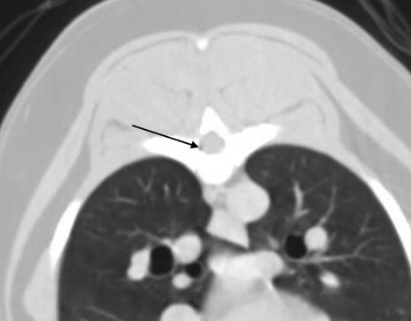

CT 촬영을 하다 보면 실제 공기방울이 심심치 않게 발견된다. 모두 의학적 이유로 발생한 것일까? 에 대한 궁금증을 풀어줄 논문이 나와 소개한다.

거기다 그 비율은

개에서 75%, 고양이에서 60% 정도가 발견된다.